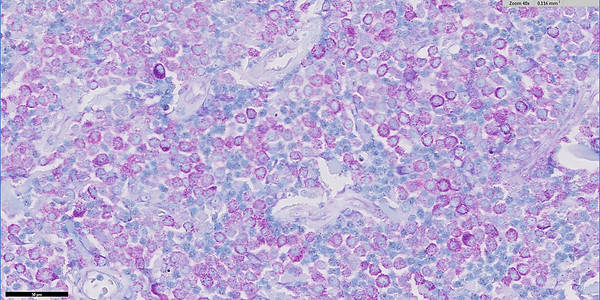

Differentiation of feline cutaneous RCTs using IHC

Davidson GA, Smith SH, Dobromylskyj MJ.

J Comp Path 2025; 219: 41-47